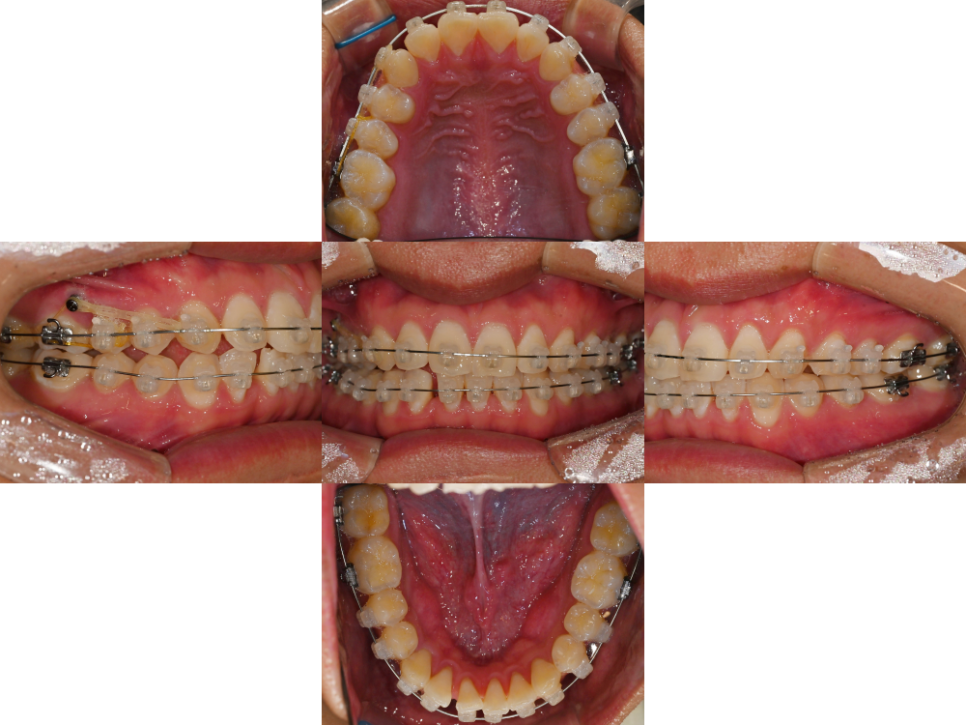

구강 내 모습을 보면

전치부에 옥니 증세가 있었습니다.

더불어, 위아래 앞니가 삐뚤빼뚤하며

위 악궁의 형태가

네모난(Square) 형태인 것을

확인할 수 있었습니다.

추가로 좌우 교합의 형태가

서로 다른 것을 알 수 있었으며,

더불어, 우측의 어금니 수평피개가

부족하여 맞물림이 원활하지 않는 것을